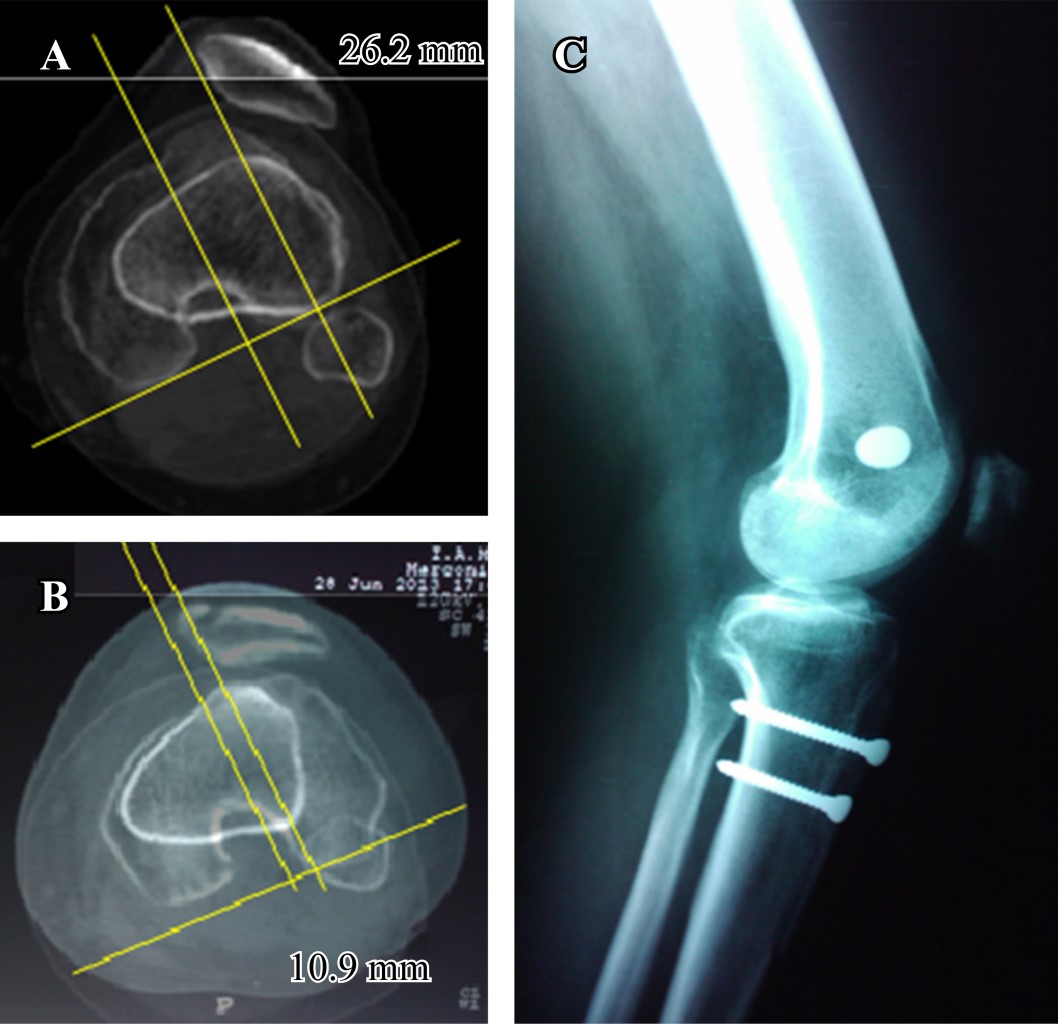

La alineación del mecanismo extensor se analiza con la tomografía computarizada midiendo la distancia de la tuberosidad tibial a la tróclea femoral (TT-TG), siendo esta misma más confiable que la medición del ángulo Q. El protocolo de tomografía computarizada superpone dos cortes, el primero a través del punto más proximal en la tróclea femoral (corte de referencia, donde la muesca del intercóndilo posterior se muestra como un arco romano) y el segundo corte a través del punto más proximal de la tuberosidad anterior de la tibia.13 Esta medida se obtiene mediante la superposición del corte axial que representa mejor la tróclea femoral y el corte axial más proximal que pasa a través de la tuberosidad tibial anterior (Figura 3). Se trazan dos líneas, una a partir de la parte inferior de la tróclea femoral y otra a través del centro de la tuberosidad tibial anterior, ambas perpendiculares a la línea condílea posterior. Esta distancia es medida en milímetros (mm). Cuando esta distancia es mayor de 20 mm predispone a la luxación rotuliana, por lo que se debería considerar realizar una osteotomía de la TAT y trasladarla a una posición más medial (en un sentido latero-medial), hasta llevar la distancia de TT-TG a un valor de 15 mm (el valor normal de esta distancia con la rodilla en extensión completa es entre 10 y 15 mm). La precisión de esta medida le permite al cirujano proponer una corrección precisa y evitar tanto una hipocorrección como una hipercorrección en la osteotomía.

La transposición latero-medial pura de la tuberosidad tibial está indicada para distancias aumentadas del TT-TG mayor de 15-20 mm en ausencia de patela alta. Se estabiliza dicha transposición con dos tornillos de 4.5 mm de diámetro (a una distancia de 20 mm entre ellos) y se sutura el periostio lateral al fragmento de hueso previamente osteotomizado (Figura 3).

El promedio del ángulo del surco troclear se modificó en los ocho casos tratados mediante la trocleoplastía. Dicho ángulo se modificó de 158o ± 19o a 140o ± 6o después de la misma (valor normal 137o ± 6o). En estos pacientes (a los cuales no se realizó osteotomía de la tuberosidad tibial anterior), el promedio de la distancia TT-TG disminuyó de 19 mm (rango 13-27 mm) a 11 mm (rango 8-17 mm) luego de la trocleplastía. Por otro lado, los pacientes que se sometieran a la transposición distal y/o medial de la tuberosidad mediante osteotomía de ésta, tuvieron una modificación en el promedio de la distancia TT-TG de 22.8 mm (rango, 20-26 mm) a 11.3 mm (rango, 6-24 mm) después del procedimiento (p ? 0.05). En este grupo el índice de Caton-Deschamps pasó de 1.26 a 0.99.